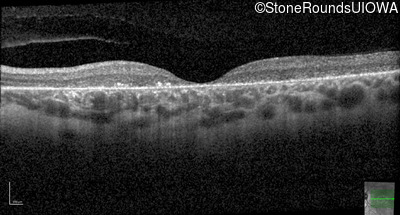

Optical Coherence Tomography - Right - 10/140 sc

Exemplar / OCT Stack

Optical Coherence Tomography - Left - 10/200 sc